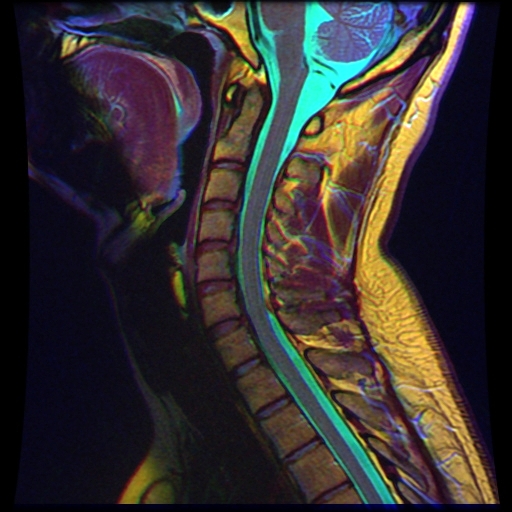

Что определяют на МРТ шеи

Синдром вертебробазилярной артерии – одна из самых частых патологий шеи у современного человека. Сидячий образ жизни, частая работа за компьютером, отсутствие гимнастики для укрепления мышц затылка – факторы раннего возникновения остеохондроза (разрушение межпозвонковых дисков), унковертебрального артроза (заострение сочленений между позвонковыми дужками), нестабильности сегмента (смещение при наклонах, резких движениях).

Комплекс описанных расстройств провоцирует не только межпозвонковых грыжи, но и компрессию позвоночной артерии, кровоснабжающей примерно 25% структур головного мозга. Симптомы недостатка микроциркуляции в вертебральном бассейне:

Синдром позвоночной артерии выявляет только 2 диагностических метода – УЗИ сосудов основания черепа, МР-ангиография. Для оценки микроциркуляции делают болюсное контрастное усиление гадолинийсодержащими препаратами.

Особенностью исследования шеи является почти 100% достоверность определения всех нарушений мягкотканого компонента. Для оценки тяжести нозологии проводится сравнение диагностических признаков и результатов магнитно-резонансной томографии.